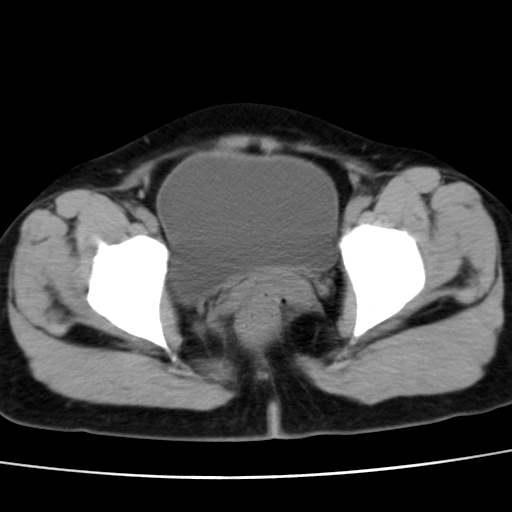

子宫多发肌瘤吗

多发性子宫肌瘤.

考虑多发子宫肌瘤,子宫直肠窝双囊性占位,另直肠周围脂肪密度增高,不知有何病史

支持考虑多发子宫肌瘤~!子宫直肠陷凹积液?

支持考虑多发子宫肌瘤~!子宫直肠陷凹积液!

子宫肌瘤,宫体部后方见液性密度影,是肠道还是子宫与直肠陷窝积液不好说,我觉得它的位置有点高

支持考虑多发子宫肌瘤!子宫直肠陷凹积液!

患者发热,而子宫直肠窝液性灶有明显边缘且局限且囊性,不除外为包裹性积液或脓肿

支持考虑多发子宫肌瘤,子宫直肠陷凹积液可能。

考虑多发子宫肌瘤

1)考虑子宫肌瘤可能性大。2)子宫后方囊性占位性病变,不排除卵巢囊肿可能。

考虑多发子宫肌瘤。子宫后方囊性占位性病变,不排除卵巢囊肿可能。